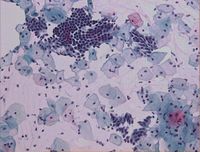

Riprende l’iniziativa del Distretto Colline dell’Albegna, Unità Funzionale consultoriale, in collaborazione con il Comitato Locale della CRI di Orbetello ed in particolare la Componente delle Infermiere Volontarie, che vede l’apertura di un ambulatorio ostetrico nei comuni di Capalbio, Sorano e Magliano con cadenza regolare ogni fine mese. In questi ambulatori sarà possibile effettuare Pap-test per le donne che rientrano nel programma di screening aziendale.

Riprende l’iniziativa del Distretto Colline dell’Albegna, Unità Funzionale consultoriale, in collaborazione con il Comitato Locale della CRI di Orbetello ed in particolare la Componente delle Infermiere Volontarie, che vede l’apertura di un ambulatorio ostetrico nei comuni di Capalbio, Sorano e Magliano con cadenza regolare ogni fine mese. In questi ambulatori sarà possibile effettuare Pap-test per le donne che rientrano nel programma di screening aziendale.